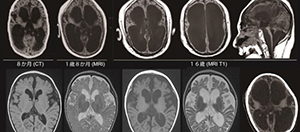

2016.09.23 小児期早期発症神経変性脳症の責任遺伝子を解明